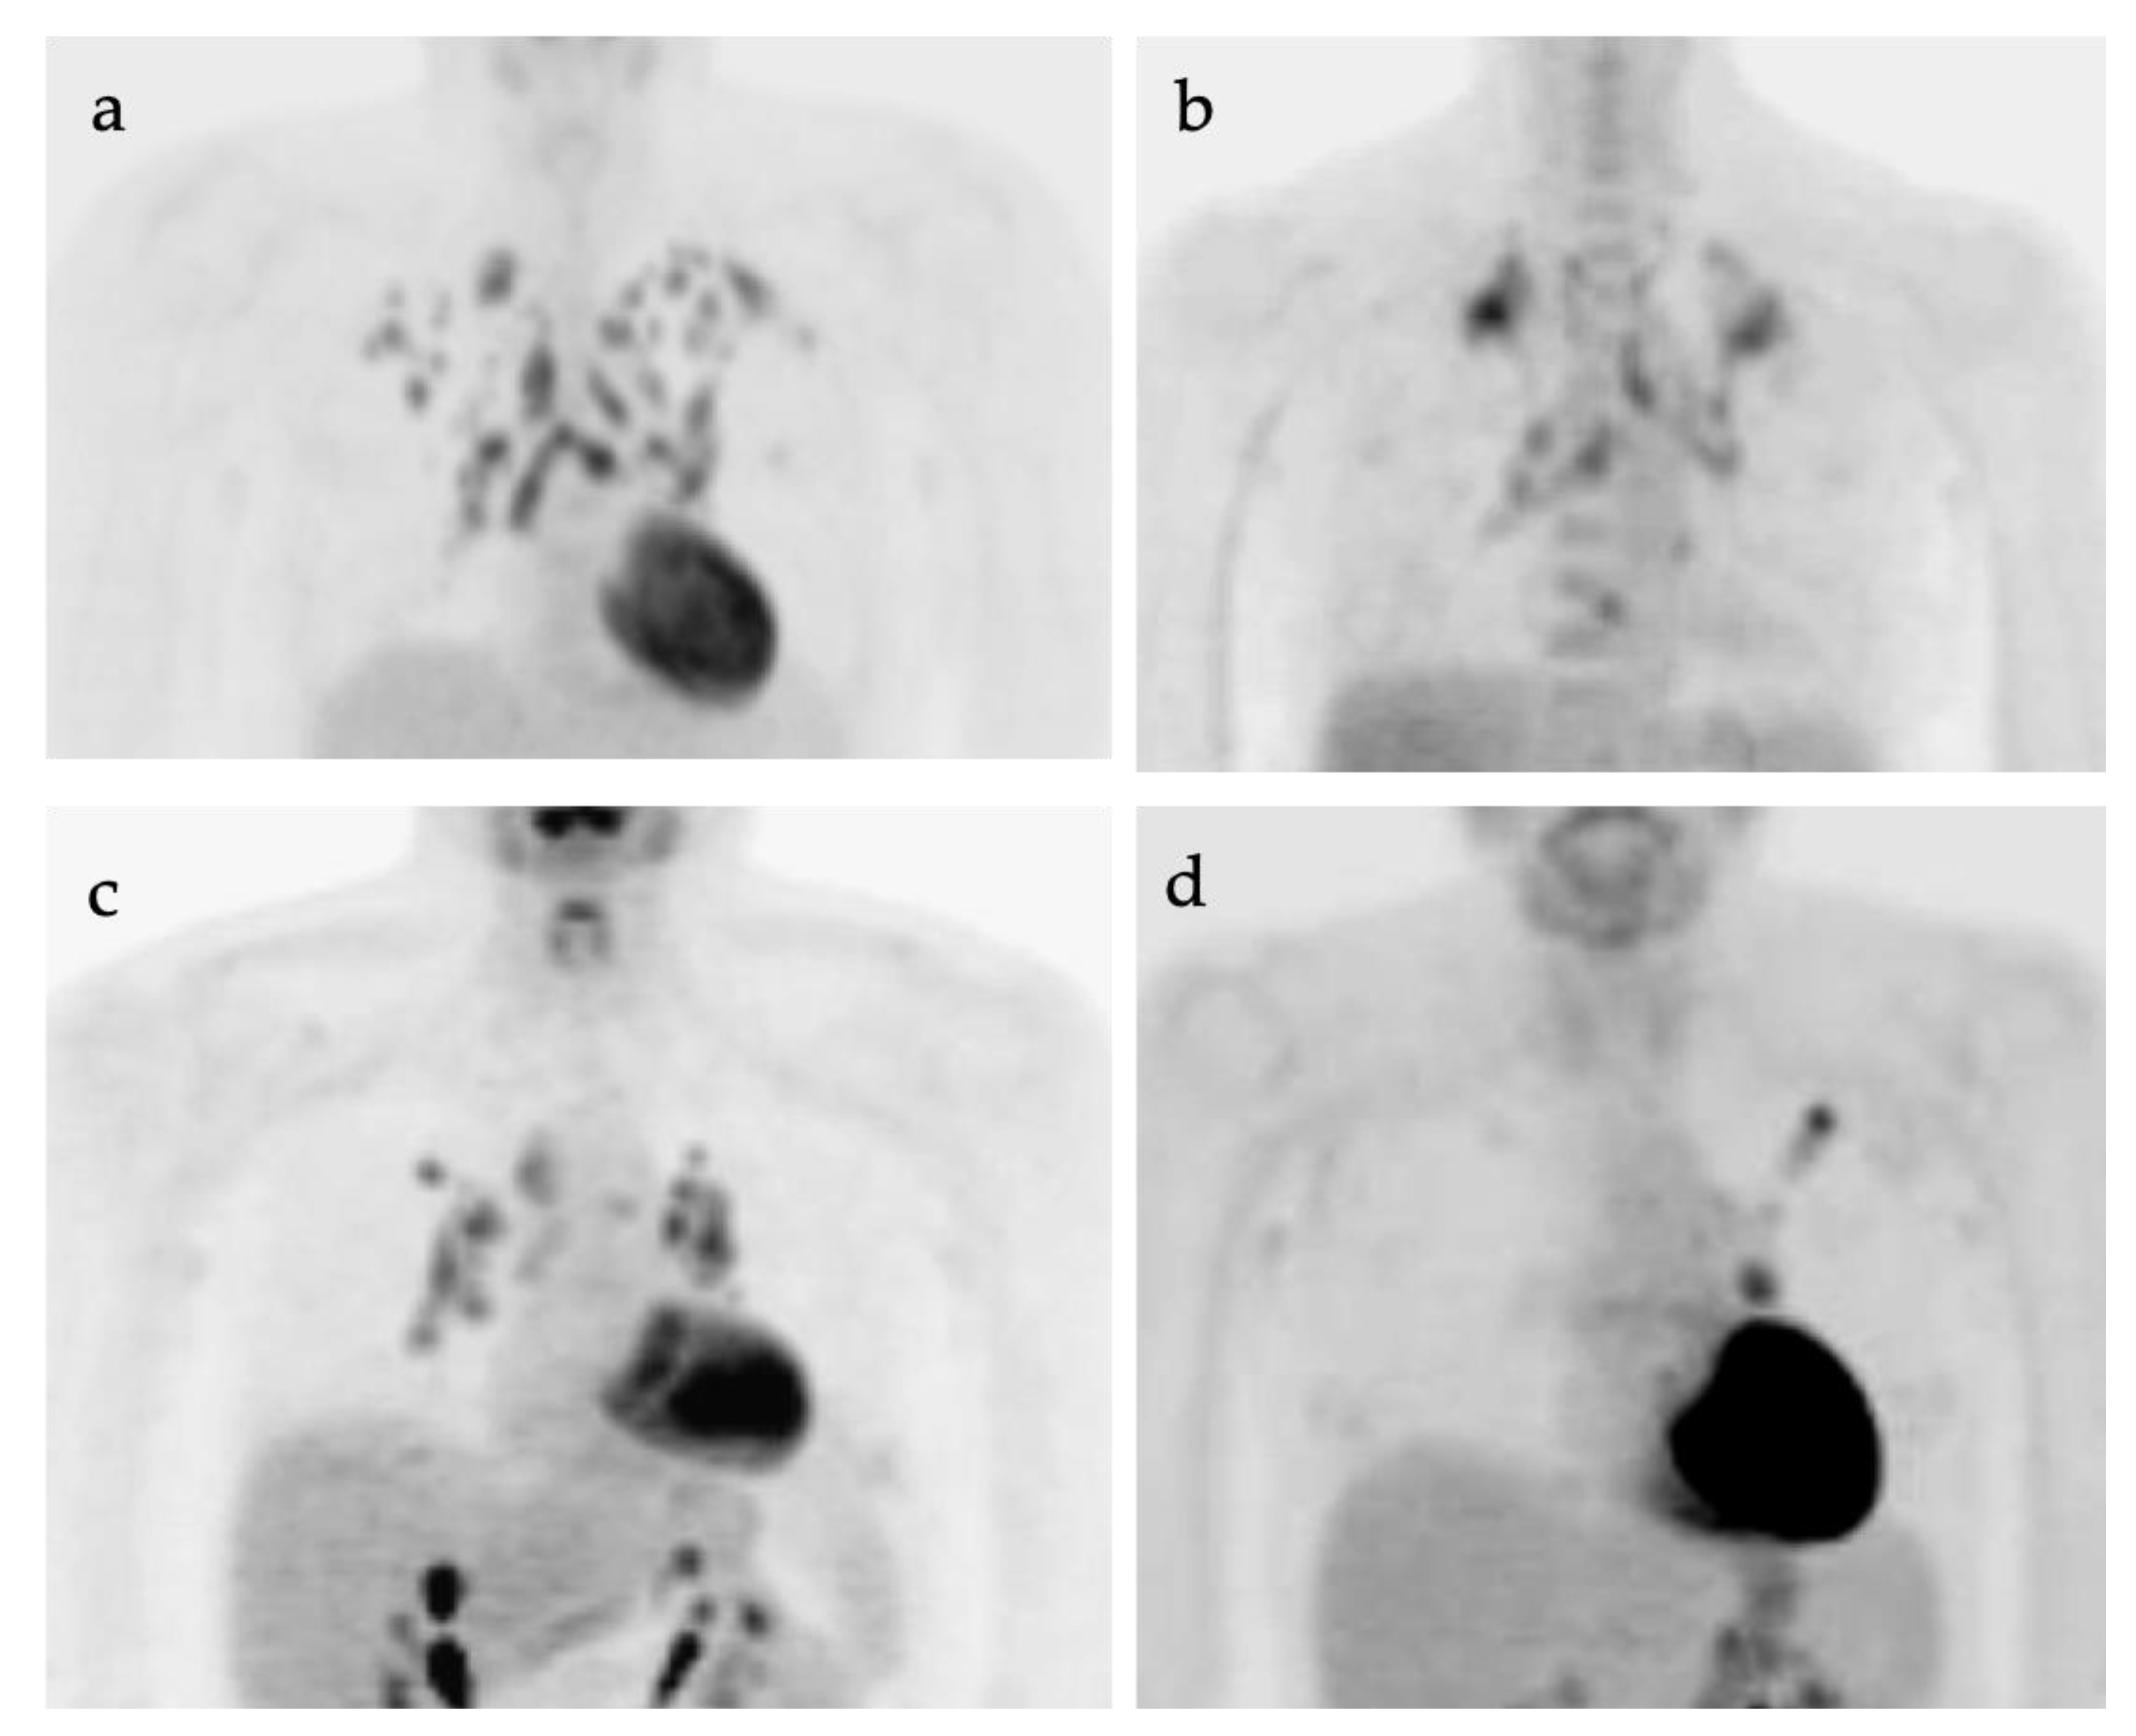

A number of diagnostic modalities have been applied to the staging of SCLC. CT of the chest, CT of the abdomen/pelvis, and MRI of the brain are the most common for staging SCLC, with inclusion of Tc-99m bisphosphonate bone scan in some cases. Multiple studies have evaluated the diagnostic accuracy of FDG PET-CT staging compared to conventional staging in patients with SCLC [45,46,47]. In a prospective study by Fischer et al., the diagnostic performance of FDG PET-CT in correctly diagnosing LD-SCLC and ED-SCLC was 95% and it was higher compared with that of conventional imaging methods with diagnostic accuracy of 85% [47]. The better diagnostic performance of FDG PET-CT in correctly staging LD-SCLC and ED-SCLC was also confirmed by another prospective study by Kishida et al., who found a diagnostic accuracy of 96.6% for FDG PET-CT compared to 91.5% correctly staged as ED-SCLC or LD-SCLC for conventional staging, although this difference was not statistically significant [45]. Few studies have also assessed the change of binary SCLC staging using FDG PET-CT compared to conventional staging (upstaging from LD-SCLC to ED-SCLC or downstaging from ED-SCLC to LD-SCLC), reporting percentages ranging from 5.1 to 21.7% [45]. A recent report supported that whole-body MRI and FDG PET-MRI may offer some advantages over FDG PET-CT and conventional CT in T-staging of the tumor, particularly in determining whether local invasion is present [48].

PET-CT has been shown to modify therapeutic interventions in up to 10–33% of patients based on the PET-CT findings [29]. Patients could benefit from correct upstaging from limited disease to extensive disease, reducing the ineffective approaches with their associated morbidity. Similarly, based on PET-CT findings, patients with indeterminate M stage could be correctly down-staged from extensive disease to limited disease and potentially offered curative treatments. As in patients with NSCLC, the targeted volume delineation for the purpose of radiotherapy planning for SCLC could be more precisely outlined by PET-CT [29].

In summary, PET-CT assessment of treatment response has been proven to be useful in SCLC, as most tumors will undergo metabolic changes before morphological changes in involved structures occur. PET-CT can detect early recurrent disease, as well as residual disease in treated tissue. It has also been demonstrated that there is a positive relationship between SUVmax values and overall survival rates in SCLC [2]. Since the natural history of SCLC indicates an unfavorable prognosis, early detection of a response to treatment is important and can be elucidated by FDG PET-CT [41].